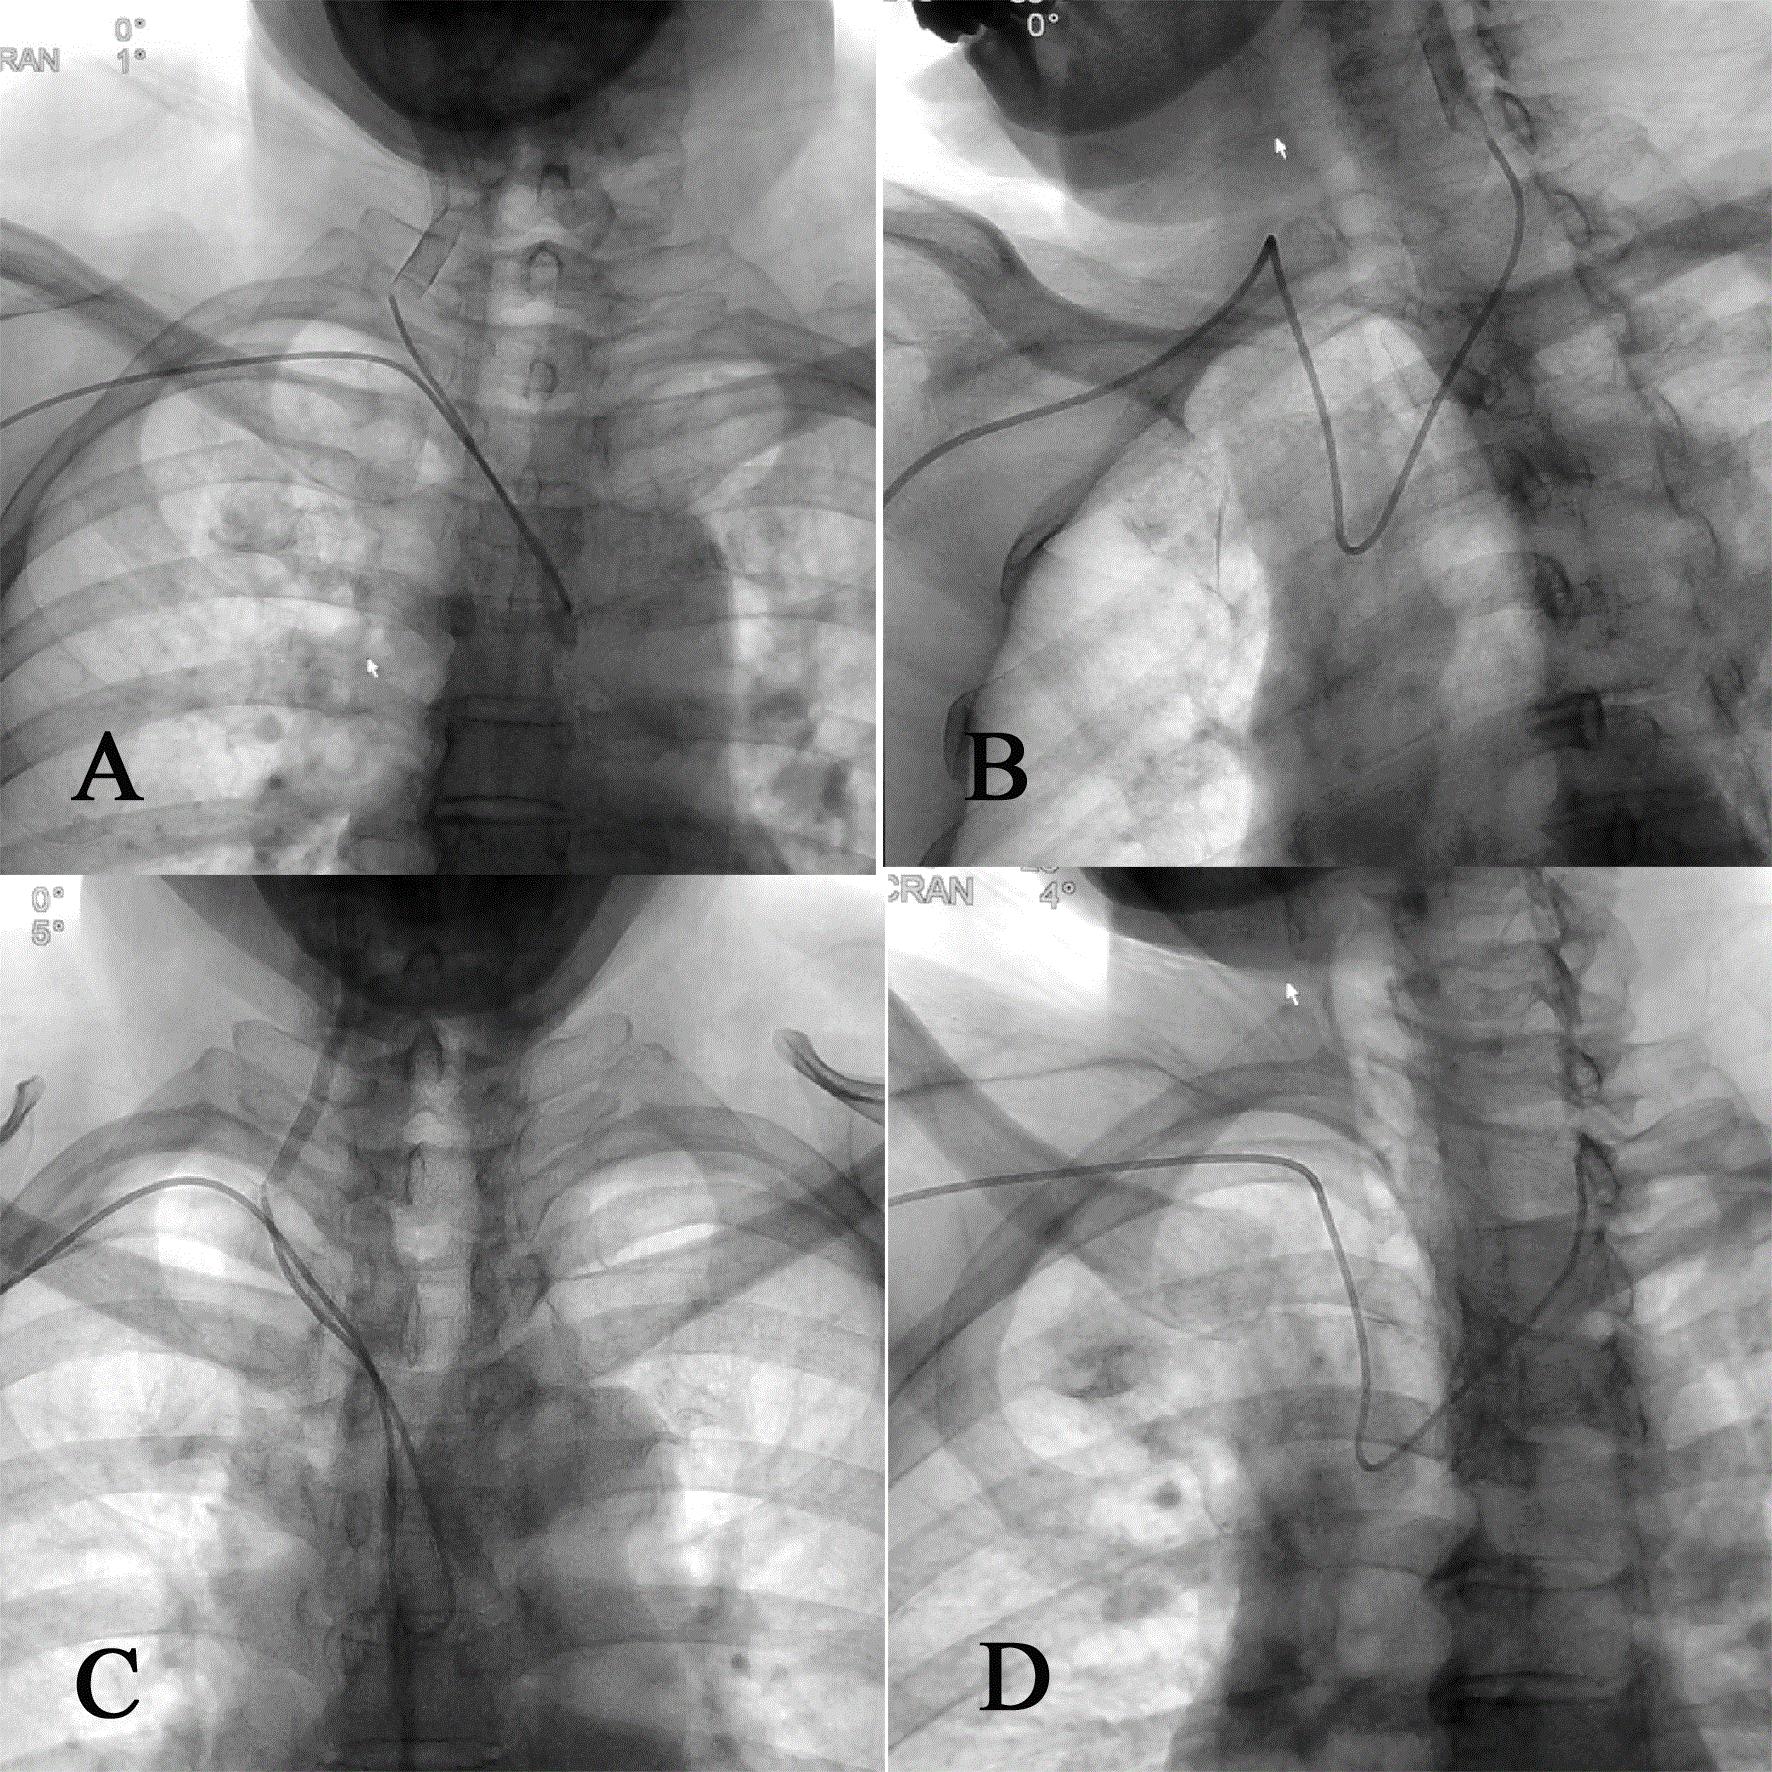

改良导管分别对左、右侧颈总动脉及左、右侧椎动脉的超选示意图。

我神经内科学科带头人罗宁博士已研发出新型经桡动脉全脑血管造影导管并获得国家专利,临床使用中取得很好的效果,该专利已与国内知名公司取得合作协议,很快将在临床进行推广。